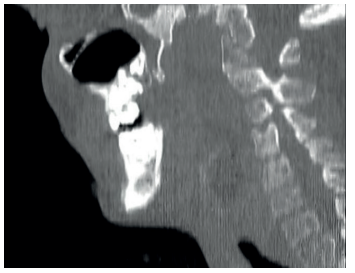

Los casos de osteonecrosis mandibular son frecuentes en pacientes con MPS tipo III y en algunos de los casos el diagnóstico se realiza en fases avanzadas por CBTC rutinarios, como mencionan Koehne y cols.30.

En los casos más avanzados resulta muy complicado realizar la exploración radiológica de manera convencional, por lo que se puede optar por TC, donde el paciente es acomodado utilizando posicionadores específicos, e incluso proceder a la sedación en ámbito hospitalario.